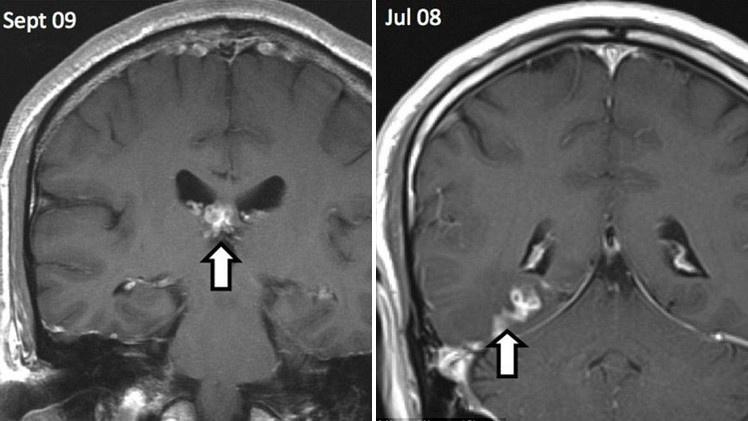

هذا المواطن من اصل صيني كان يعاني من آلام في الرأس منذ سنوات، ويشكو من ضعف الذاكرة، ويشم روائح غريبة تنبعث من رأسه. أكتشف الأطباء بنتيجة التصوير المغناطيسي لرأسه عام 2008 ان قشرة دماغه مصابة بأضرار غريبة تبلغ مساحتها زهاء 5 سم.

في عام 2012 أكتشف الأطباء وجود دودة شريطية في انسجة دماغ الرجل، طولها 10 سنتيمترات، فاضطروا الى اجراء عملية جراحية لاستئصالها . ومع ذلك لا يزال هذا الرجل يعاني من نفس المشاكل السابقة.